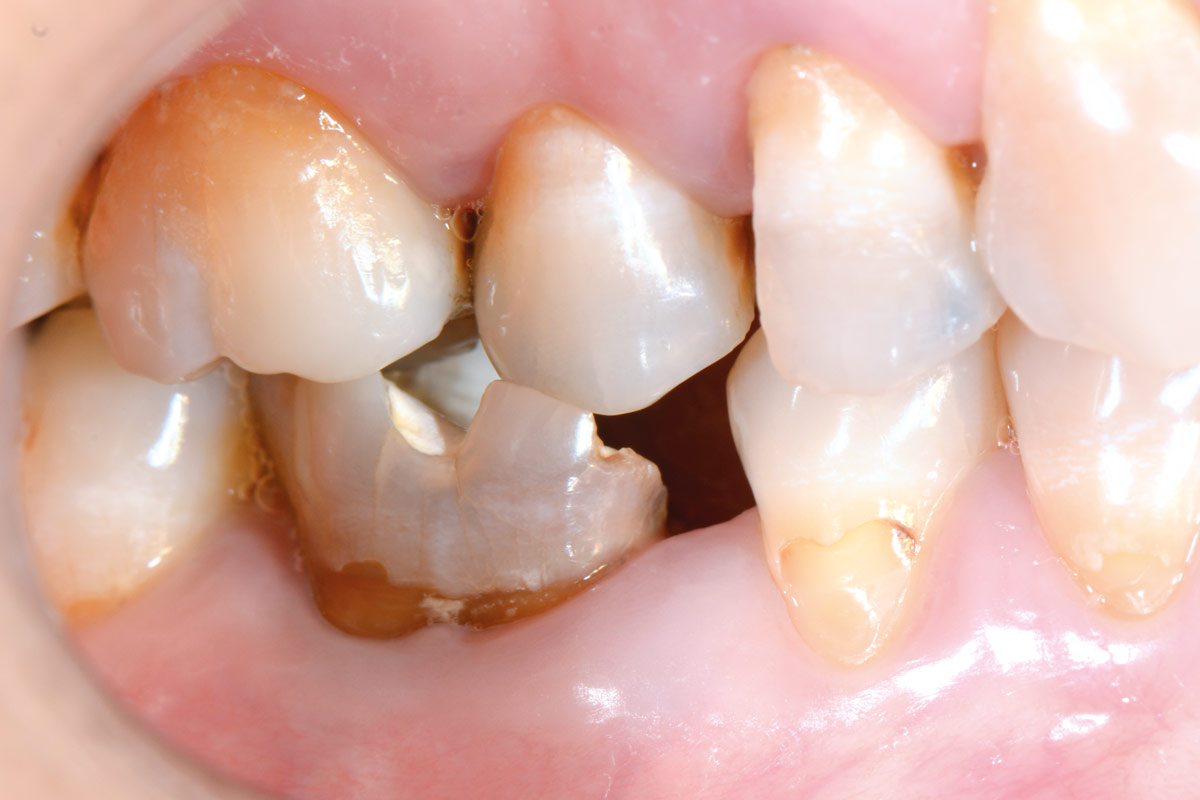

5/19 - Initial clinical situation before extraction and implantation

Immediate implant placement using maxresorb® - Dr. Alejandro Signorio